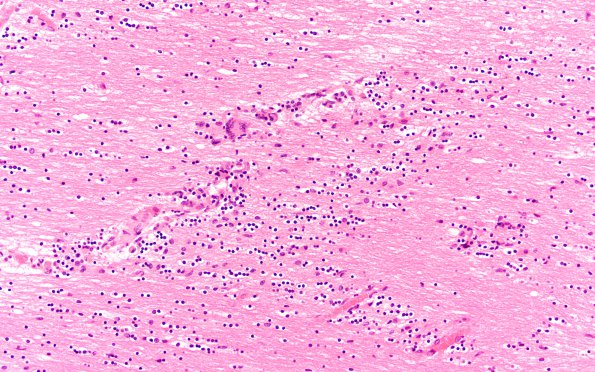

Washington University Experience | INFECTION | Viruses | HIV | HIV Encephalitis | 3B1 Encephalitis, HIVL (& minor HIVE) (Case 3) H&E 40X

Pathology in this case was predominantly focused on the white matter in which inflammatory cells and multinucleated giant cells were numerous. (H&E)